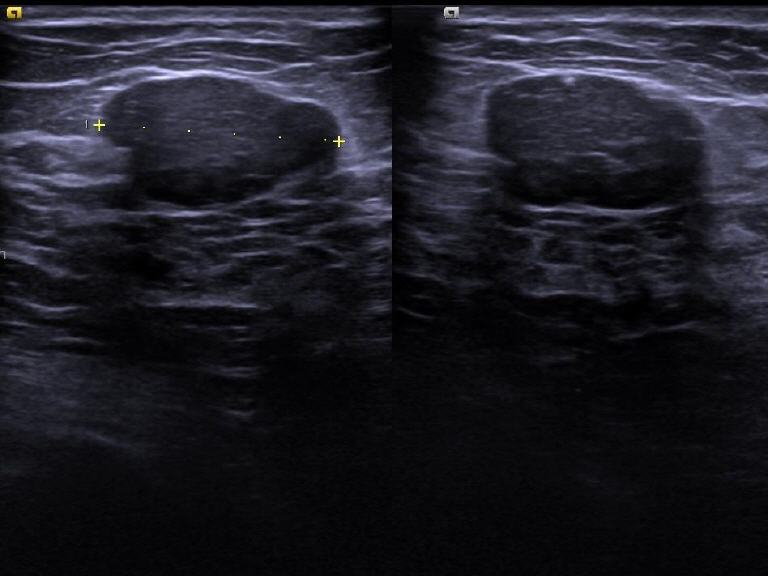

• Sonographiebild der Brust mit Herdbefund

Hier sieht man einen dunklen (hypoechogenen), glatt begrenzten Herdbefund im Brustparenchym. Der Befund kann gut oder bösartig sein und sollte mit einer Biopsie abgeklärt werden.